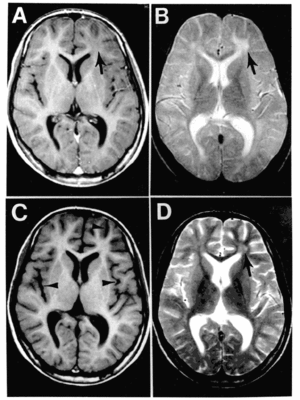

Characteristic periodic activity (Rademecker complex) is seen on electroencephalogram (EEG) showing widespread cortical dysfunction; pathologically, the white matter of both the hemispheres and brainstem are affected, as well as the cerebral cortex, and eosinophilic inclusion bodies are present in the nuclei of neurons (gray matter) and oligodendrocytes (white matter).[5] The diagnosis of SSPE is based on signs and symptoms (Changes in personality, a gradual onset of mental deterioration and myoclonia) and on test results, such as typical changes observed in EEGs, an elevated anti-measles antibody (IgG) in the serum and cerebrospinal fluid, and typical histologic findings in brain biopsy tissue.